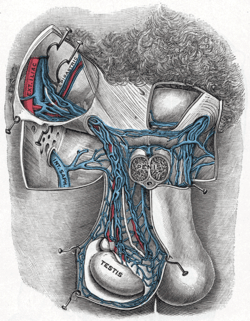

The relations of the viscera and large vessels of the abdomen (posterior view). Transverse section through the left side of the scrotum and the left testis.

Transverse section through the left side of the scrotum and the left testis. Testis, spermatic vessels and vas deferens

Testis, spermatic vessels and vas deferens- Testicular artery and vein